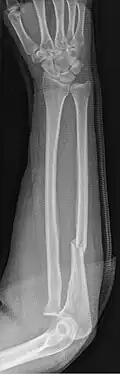

| Monteggia Fracture (type of ulna fracture) | |

- Monteggia fracture - a fracture of the near to elbow end of the ulna with the dislocation of the head of the radius at the elbow joint.[2]

Monteggia Fracture (fracture of proximal ulna) -